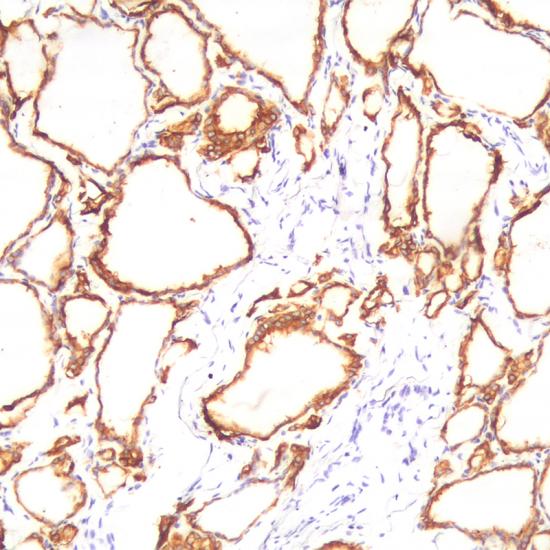

TPO抗體試劑(免疫組織化學(xué)) 閩廈械備20180119號(hào)

• 預(yù)處理:

熱修復(fù)

• 陽(yáng)性部位:

細(xì)胞漿

• 陽(yáng)性對(duì)照:

甲狀腺乳頭狀癌

• 適用組織:

石蠟

甲狀腺過氧化物酶(TPO)是甲狀腺激素合成過程中的關(guān)鍵酶。TPO在正常的甲狀腺組織或良性的甲狀腺腫瘤中高表達(dá),在甲狀腺惡性腫瘤中低表達(dá)。該抗體主要用于甲狀腺良、惡性腫瘤的鑒別診斷。